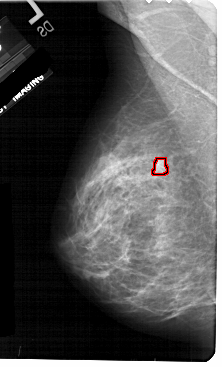

A_1725_1.LEFT_MLO

LEFT_MLO LINES 5491 PIXELS_PER_LINE 3316 BITS_PER_PIXEL 12 RESOLUTION 43.5 OVERLAY

FILE: A_1725_1.LEFT_MLO.OVERLAY

TOTAL_ABNORMALITIES 1

ABNORMALITY 1

LESION_TYPE MASS SHAPE FOCAL_ASYMMETRIC_DENSITY MARGINS ILL_DEFINED

ASSESSMENT 4

SUBTLETY 3

PATHOLOGY MALIGNANT

TOTAL_OUTLINES 1

BOUNDARY